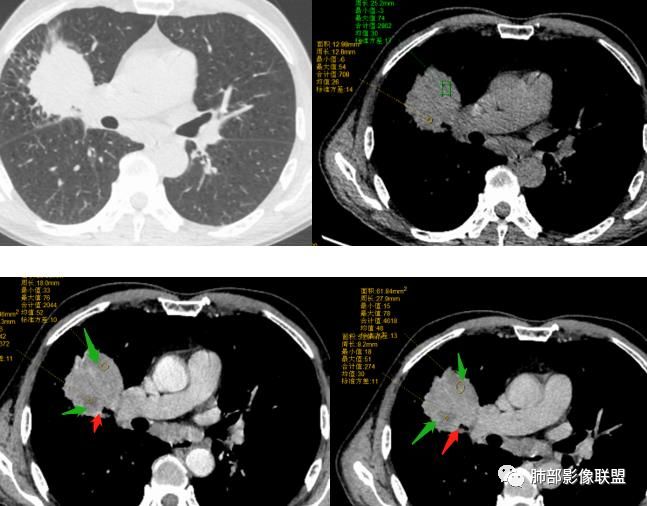

患者中老年男性,体检发现右肺占位。血常规轻度贫血,AFP、CEA正常,肝肾功能、血糖、血脂、心肌酶、电解质正常。胸部CT:右肺中叶巨大肿块灶,垮叶生长,可见分叶、毛刺、血管集束、支气管截断征象,远端周围可见小叶间隔增厚,增强轻度强化,内可见低密度坏死区,综合淋巴结肿大,且可见淋巴结内似低密度灶。综合考虑恶性,鳞癌并癌性淋巴管炎可能大。鉴别结核、腺癌。

胸CT:右肺中叶团块样实性占位,边缘膨隆,中叶外侧段阻塞,病灶可见深分叶、棘突,胸膜牵拉;增强不均匀强化,可见边缘模糊血管影,病灶内大片状低密度区,纵隔多发肿大淋巴结。

首先临床资料没有特别提示。影像上首先背景是肺气肿背景,这个是肺癌的危险因素。

淋巴结肿大,且坏死,不均强化

病灶内不均匀强化。支气管堵塞

边缘膨隆。内血管毛糙纤细

中叶支气管堵塞,但是也有推移

跨叶,累及三个叶